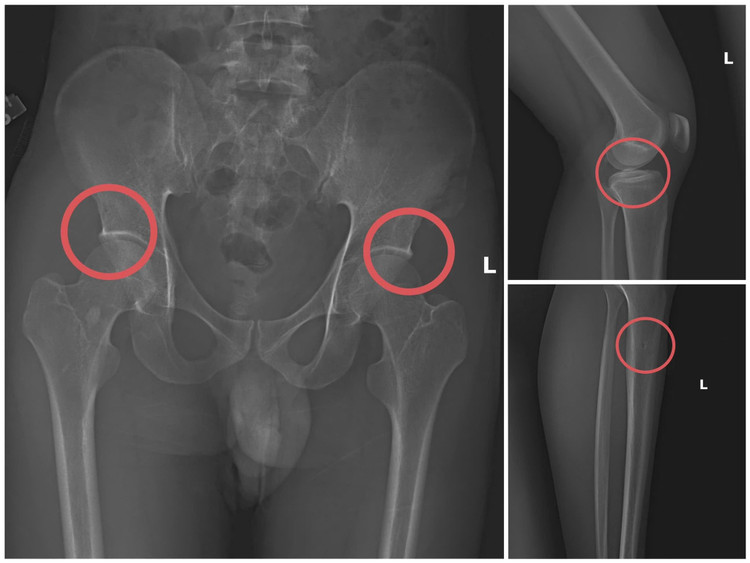

Bản phim chụp XQ một số tổn thương xương do đối tượng tạo ra

Điều tra xác định, Châu trực tiếp tiêm thuốc mê rồi dùng kim tiêm, búa, đinh tác động vào xương người mua bảo hiểm, tạo nên các vết nứt, vỡ xương tương tự tai nạn thật. Khi tạo xong thương tích, Châu hướng dẫn các đối tượng dựng hiện trường giả như điện giật ngã, trượt chân ngã suối, nhằm hợp thức hóa bệnh án, hoàn thiện hồ sơ yêu cầu chi trả.